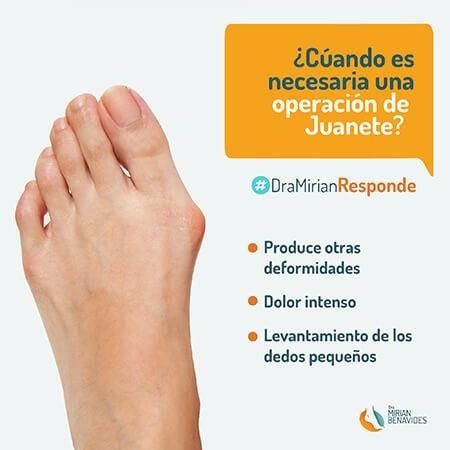

Tenia juanetes. La Dra. me realizó un procedimiento de artrodesis muy exitoso para mejorar la deformidad de mis dedo y el dolor que sentia.